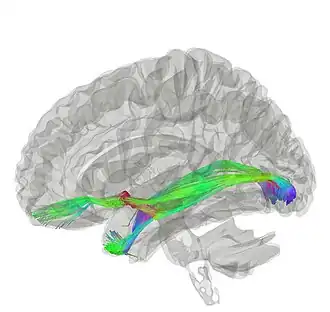

Tractography of anterior commissure

Averaged tracking results of ten normal controls showing the anterior commissure. Image from Winter and Franz (2014)[2]

The functionality of the anterior commissure is still not completely understood. Researchers have implicated it in functions ranging from colour perception to attention. One such study supported colour perception in callosal agenesis (those born without a corpus callosum; Barr & Corballis, 2002).[3] Other studies have built on this to imply that the anterior commissure can be a compensatory pathway in those without a corpus callosum, presenting diffusion tensor imaging (DTI) techniques to better elucidate the anterior commissure and how it might be implicated in various functions (Winter & Franz, 2014).[2]